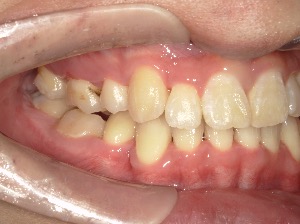

before

after

患者さんの年齢 20代 女性 症状 ガタガタを治したい 治療内容 マウスピース矯正治療 費用 90万(税抜) 治療期間・回数 治療期間2年、通院回数10回 メリット 笑顔が綺麗 デメリット・リスク 期間がかかることがある - マウスピース矯正